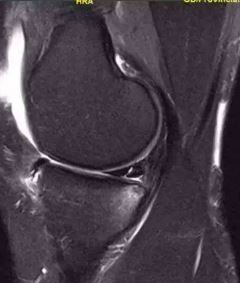

0级:正常的半月板形态规则,表现为均匀一致的低信号。

(0级:半月板均一的低信号)